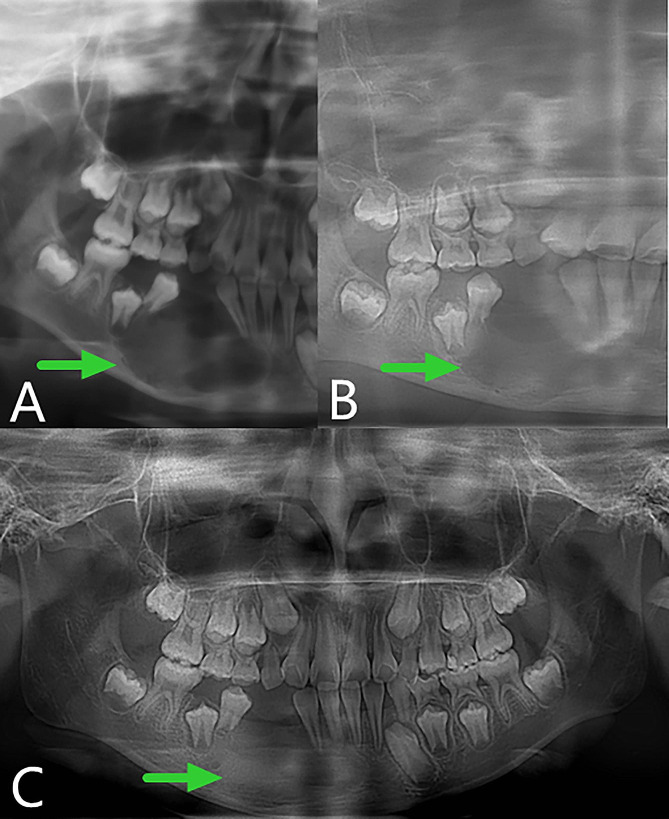

The right face and mandibular angle area were dilated, the skin color and temperature were normal, the mouth opening was limited, and there was no numbness in the lower lip. The right mandibular posterior tooth vestibular sulcus and ascending branch were seen in the mouth, the palpation was hard, there was no ping-pong-like sensation, the mucous membrane was intact, and the tooth 46 was II °loose. As shown in Fig. 1, the preoperative panoramic radiography revealed a typical AM: multilocular cystic low-density shadow of different sizes, overlapping each other, clear boundaries, and AM-involving teeth with truncated root resorption.

Fig. 1.

Preoperative panoramic radiography showing a typical AM in the right mandible

Fig. 3.

Panoramic oral radiogram. A, 3 months after the operation. B, 6 months after the operation. The original osteogenic area (A, red curve) disappear compared with B

Fig. 4.

Follow-up panoramic oral radiogram after the second operation, displaying the continuous bone remodeling. A, 3 months postoperative. B, 4 months postoperative. C, 6 months postoperative. D, 10 months postoperative

Fig. 5.

Follow-up images. A, B and C, Cone beam computed tomography showing 5, 7,10 months respectively after the second operation. D and E, Computed tomography view displaying the continuous osteogenic remodeling 4 and 15 months after the window is closed. F, Panoramic oral radiogram demonstrating 15 months after the surgery to close the window